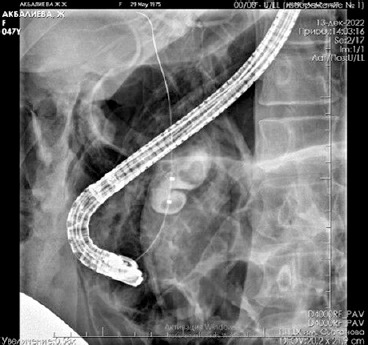

During the procedure, subcutaneous emphysema of the chest, neck, and face was identified, suggesting a possible rupture of the choledochal cyst wall and the entry of air from the abdominal cavity into the mediastinum. To close the rupture of the choledochal cyst, it was decided to place an endobiliary stent. A metallic fully covered endobiliary stent, 6.0 cm in length, was placed in the CBD. After the stent placement, bile began to flow through the stent (Figure 4). After the placement of the endobiliary stent, no further progression of the subcutaneous emphysema was noted.

Figure 4

A – Catheterization of the common bile duct with a papillotome over a guidewire. B – Endoscopic papillosphincterotomy up to 0.7 cm with additional balloon dilation. C – Choledocholithotripsy. D – Insertion of a self-expanding metal stent